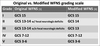

What are the two commonly used scales for SAH grading

Fisher grading (Modified fisher)

WFNS

Features of Fisher grading

Use the amount of blood seen on CT to predict the subsequent risk of radiological vasospasm.

1-4.

Issues with original Fisher grading

Used an early CT scanner with images printed on films. Measured manually with rulers, theefore measurements only apply to images obtained on scanner.

Patients could also be classified into more than one grade

Fisher 1

No blood on CT scan